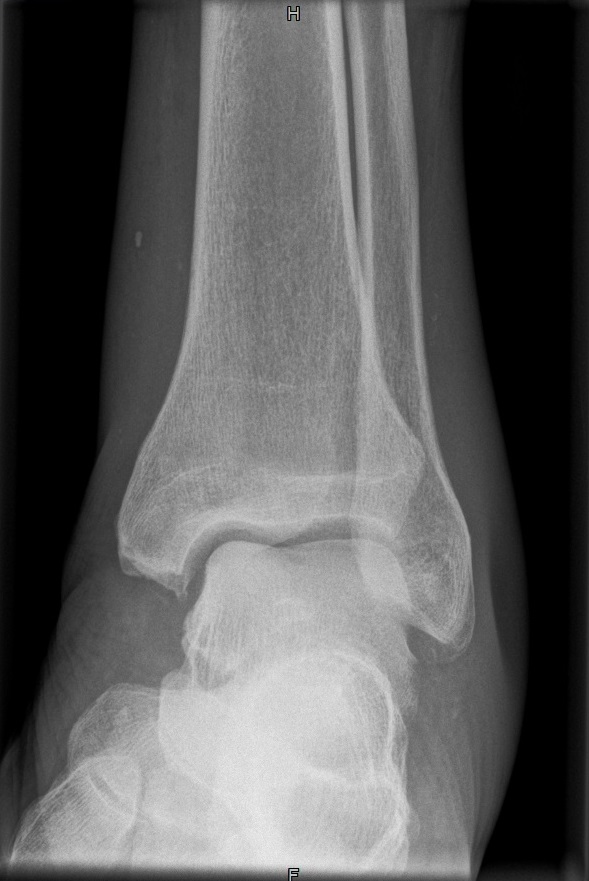

OSG seitlich

Fehler

Doppelkonturierung im oberen Teil der Talusrolle. Die Beurteilung des OSG ist nicht möglich. Die Spitze des Malleolus lateralis steht höher als die Spitze des inneren Malleolus.

Abhilfe

Der Fuß muss gesamthaft etwas höher gelagert werden, bei streng seitlicher Zentrierung.